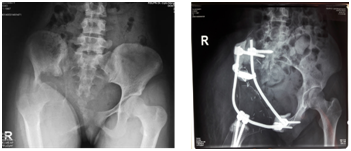

The surgery lasted for 12hours with 4000ml blood loss. We performed wide marginal excision Post-operative X ray showed interconnecting pedicle and rodsystem reconstructed the pelvicarch (Figure 2). The histopathological examination revealed a grade 2 chondrosarcoma with superior, medial, lateral and distal margin were tumor-free.

Figure 2 Pelvic AP plain radiograph. a. Pre-operative; b. Post-operative.